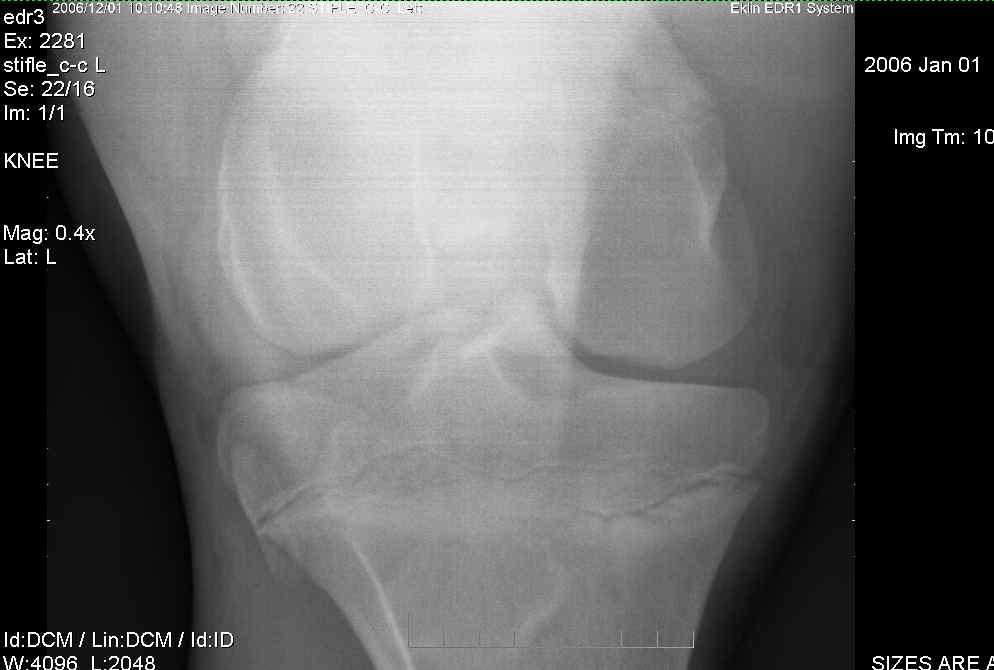

Left Stifle-1

Left Stifle-2

Left Stifle-3

I am sorry to meet you over such a serious problem. I am currently traveling so don't have access to my library where I might be able to provide you with more precise prognostic information but the OCD lesions on the trochlear ridges of both stifles are remarkable and often result in chronic lameness with secondary DJD of the stifles. Therefore surgery would be recommended and the prognosis from the radiographs alone would be guarded for future athletic potential but should really wait until the arthroscopic surgery when a better idea of the pathology in the joint can be better characterized. The horse should not be bred because of genetic predisposition for such lesions. Is there effusion (swelling) in the stifle yet?

This is how my vet explained the xrays to me: On the first xray, look at the top-left bone (femur). The bottom of it should have a smooth curve going all the way around, but the bottom of the femur shows up darker on the xray, and the edge is sheared off. This lesion is less dense (softer) than the rest of the bone. In surgery, they would take out the lesion (all of the damaged area), and fill it back in new material. The first 4 pics are her right stifle, the last three pics are her left stifle. On the first pic of her left stifle (fifth picture in the post) look at the bottom edge of the bone on the top right. Again, you can see the damaged edges. On the last pic, I think there is another area of OCD showing up on the top-right side. Maybe Dr. O. can better clarify the areas we are looking at if I am incorrect, or if I am missing anything else.